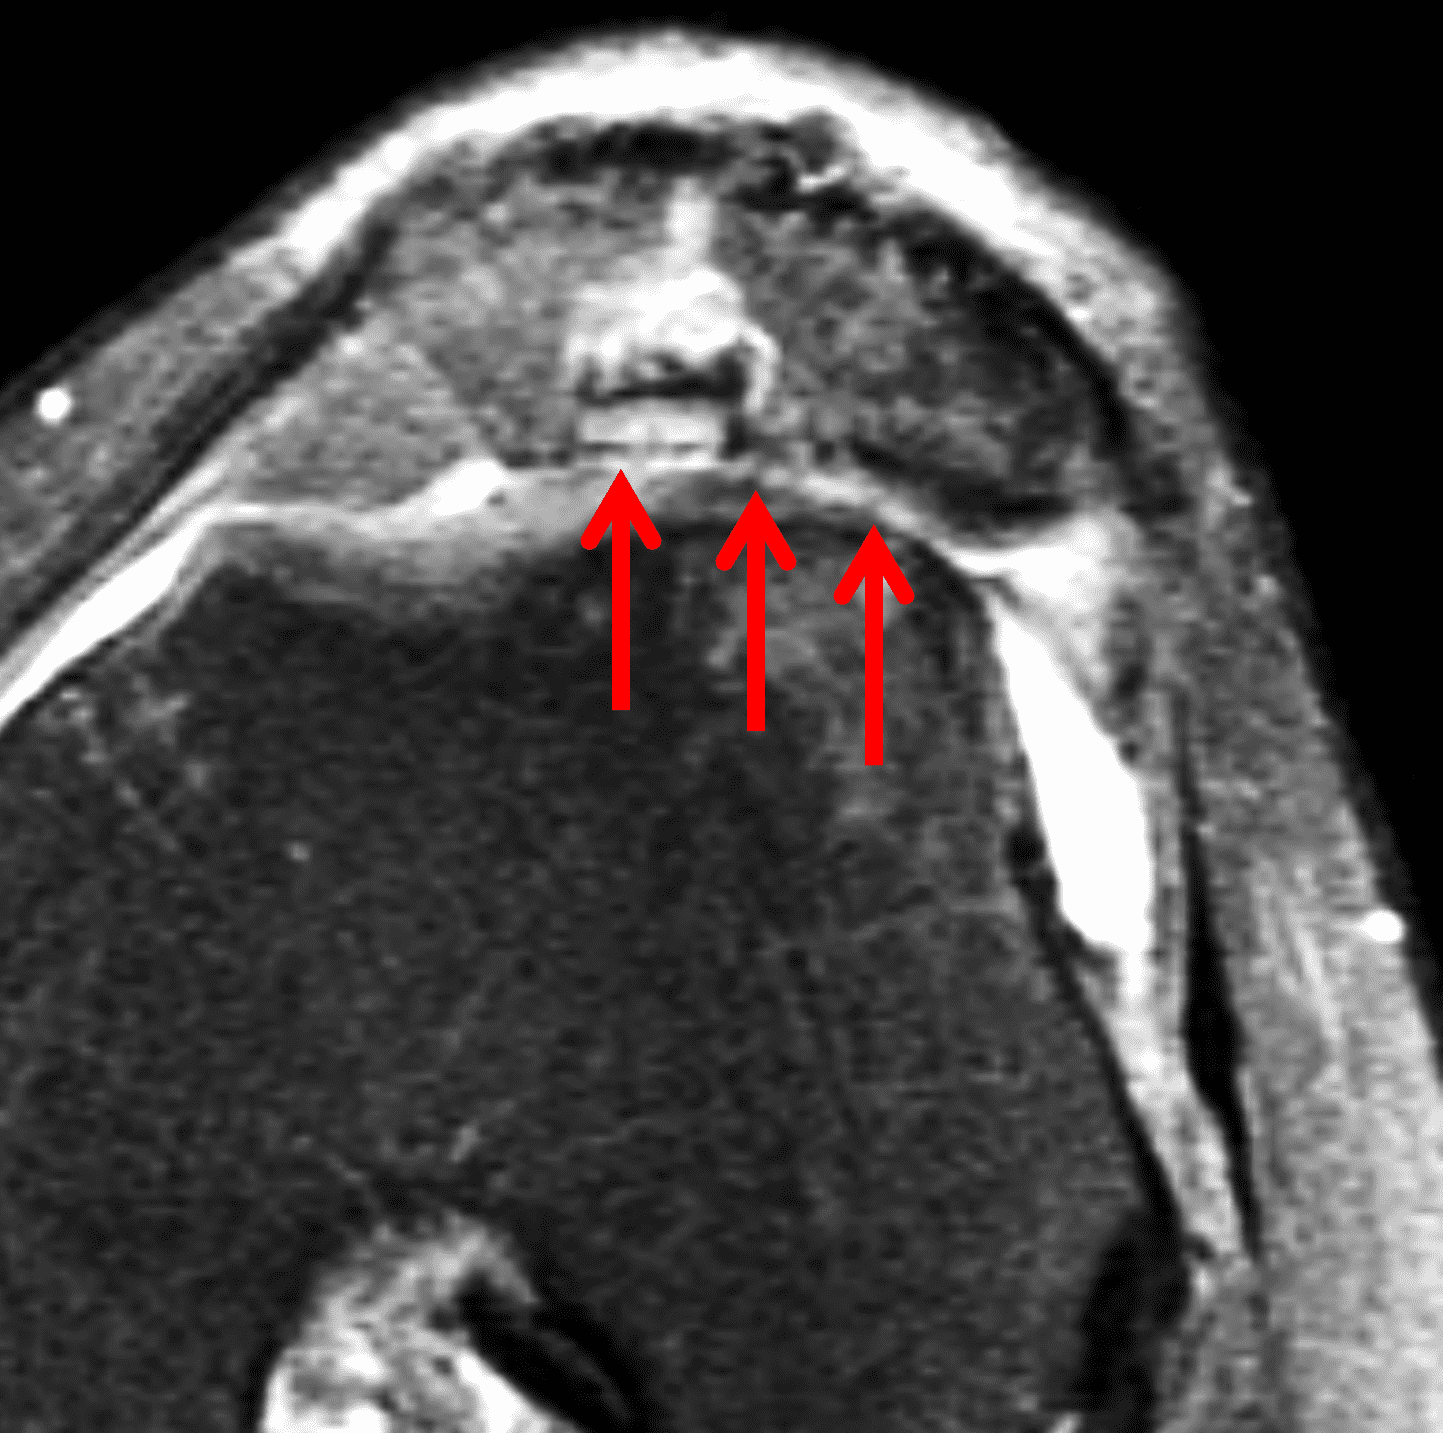

A 32-year-old man suffered a traumatic chondral injury to the medial femoral condyle that was treated with an osteochondral allograft 20 months previously. Representative images from a current knee MRI include (1A) coronal fat-suppressed fluid-sensitive and sagittal (1B) T1-weighted, (1C) proton density-weighted, and (1D) T2-weighted sequences. Are the post-operative MRI findings normal and expected, or abnormal and pathologic? Based on these images, would you characterize the procedure as a success or failure?

Figure 2: (2A) On the coronal image, the margins of the osteochondral graft are faintly visible (arrowheads). Both the graft and underlying bone show mild marrow edema, an expected finding. (2B) The T1-weighted image shows continuity of the marrow in the graft (asterisks) with the underlying bone, indicating osseous integration. A bioabsorbable pin (arrow) used for graft fixation is partly visible. (2C) The proton density-weighted image shows a low signal intensity seam (black arrow) between the native cartilage and transplant, as well as a defect in the subchondral bone plate of the graft (red arrow) where the pin was drilled, both normal findings. (2D) The T2-weighted image shows a smooth, congruent articular surface (arrows), restoring the normal anatomy, and a tiny subchondral cyst. No findings are present to suggest graft failure. The patient’s current symptoms were attributed to pathology elsewhere in the joint (not shown).

The postoperative imaging appearance of osteochondral allografts is similar to autografts (Figure 2).33 The subchondral bone plate of the donor and recipient sites do not have to match, but the articular surface should be congruent. Grafts that fail to incorporate by one year have a poor prognosis. Persistent marrow edema (beyond 12 months), a thick graft interface containing cysts or fluid, and subsidence of the graft are associated with poor osseous healing and worse outcomes. Extensive host marrow edema and severe synovitis may be a clue to immunologic rejection of the graft (Figure 18).21, 34